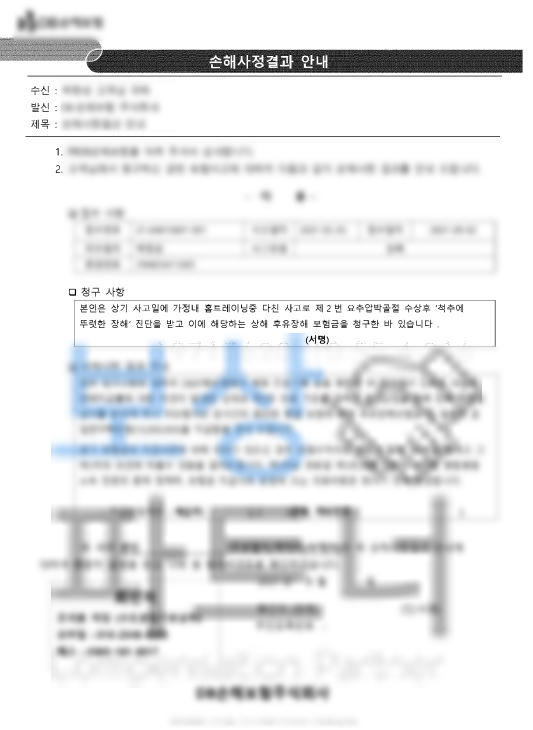

위 보험증권을 보시면 기본, 주 계약에도 있을 수 있고 그 외 특약으로도 있을 수 있습니다. 저희 손해사정팀은 의뢰인에게 보상 과정과 범위를 안내해드리기 위해 영상CD, 진료기록, 보험증권 등을 요청했고 의뢰인께서 적극적으로 협조해주셔서 후유장해 보상 가능성을 확인할 수 있었습니다.

04년 9월 가입한 생명보험사, 08년 9월 가입한 손해보험사, 02년 8월 가입한 옛날 급수보험 과거 가입한 옛날 보험들이 많으셨어요.

저희는 십 수년 경력의 경험, 지식, 노하우들을 녹여낸 손해사정 보고서를 작성하여 의뢰인의 장해의 적정성을 주장했죠. 물론 보험사에서도 현장조사를 실시하며 적지않은 보험금 이었기에 첨부보완 등의 각종 요청, 요구가 있었습니다.

후유장해 보험금 총 49,454,000원

약 5천만원의 후유장해보험금

수령하실 수 있었습니다. 2000년대 초반에 가입한 종신, 생명 보험사의 상품들이 6급에도 높은 금액으로 형성되었고 의뢰인 또한 개인의 장해에 대해 보상파트너 통해 적정성을 증명하셨기에 약 5천만원의 후유장해보험금 이끌어낼 수 있었습니다.